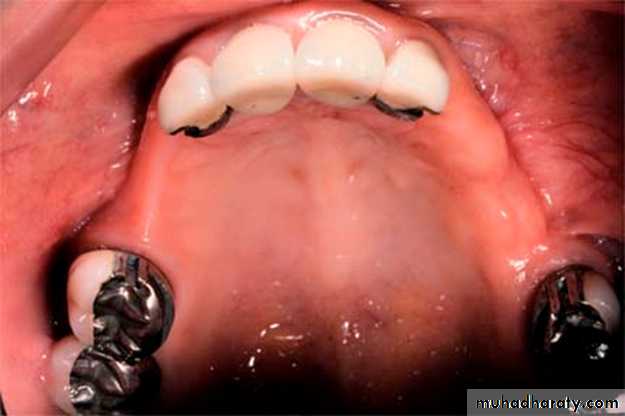

Partial denture: A prosthesis that replaces one or more, but not all of the natural teeth and supporting structures. Its supported by the teeth and/or the mucosa. It may be fixed( i.e. a bridge) or removable.Removable partial denture (RPD): A partial denture that can be removed and replaced in the mouth by patient. A partial denture being constructed from cobalt chromium alloy and considered to be as permanent treatment.

• Abutment: a natural tooth that support a partial denture.

• Retainer: a component of partial denture that provides both retention and stability for the partial denture.